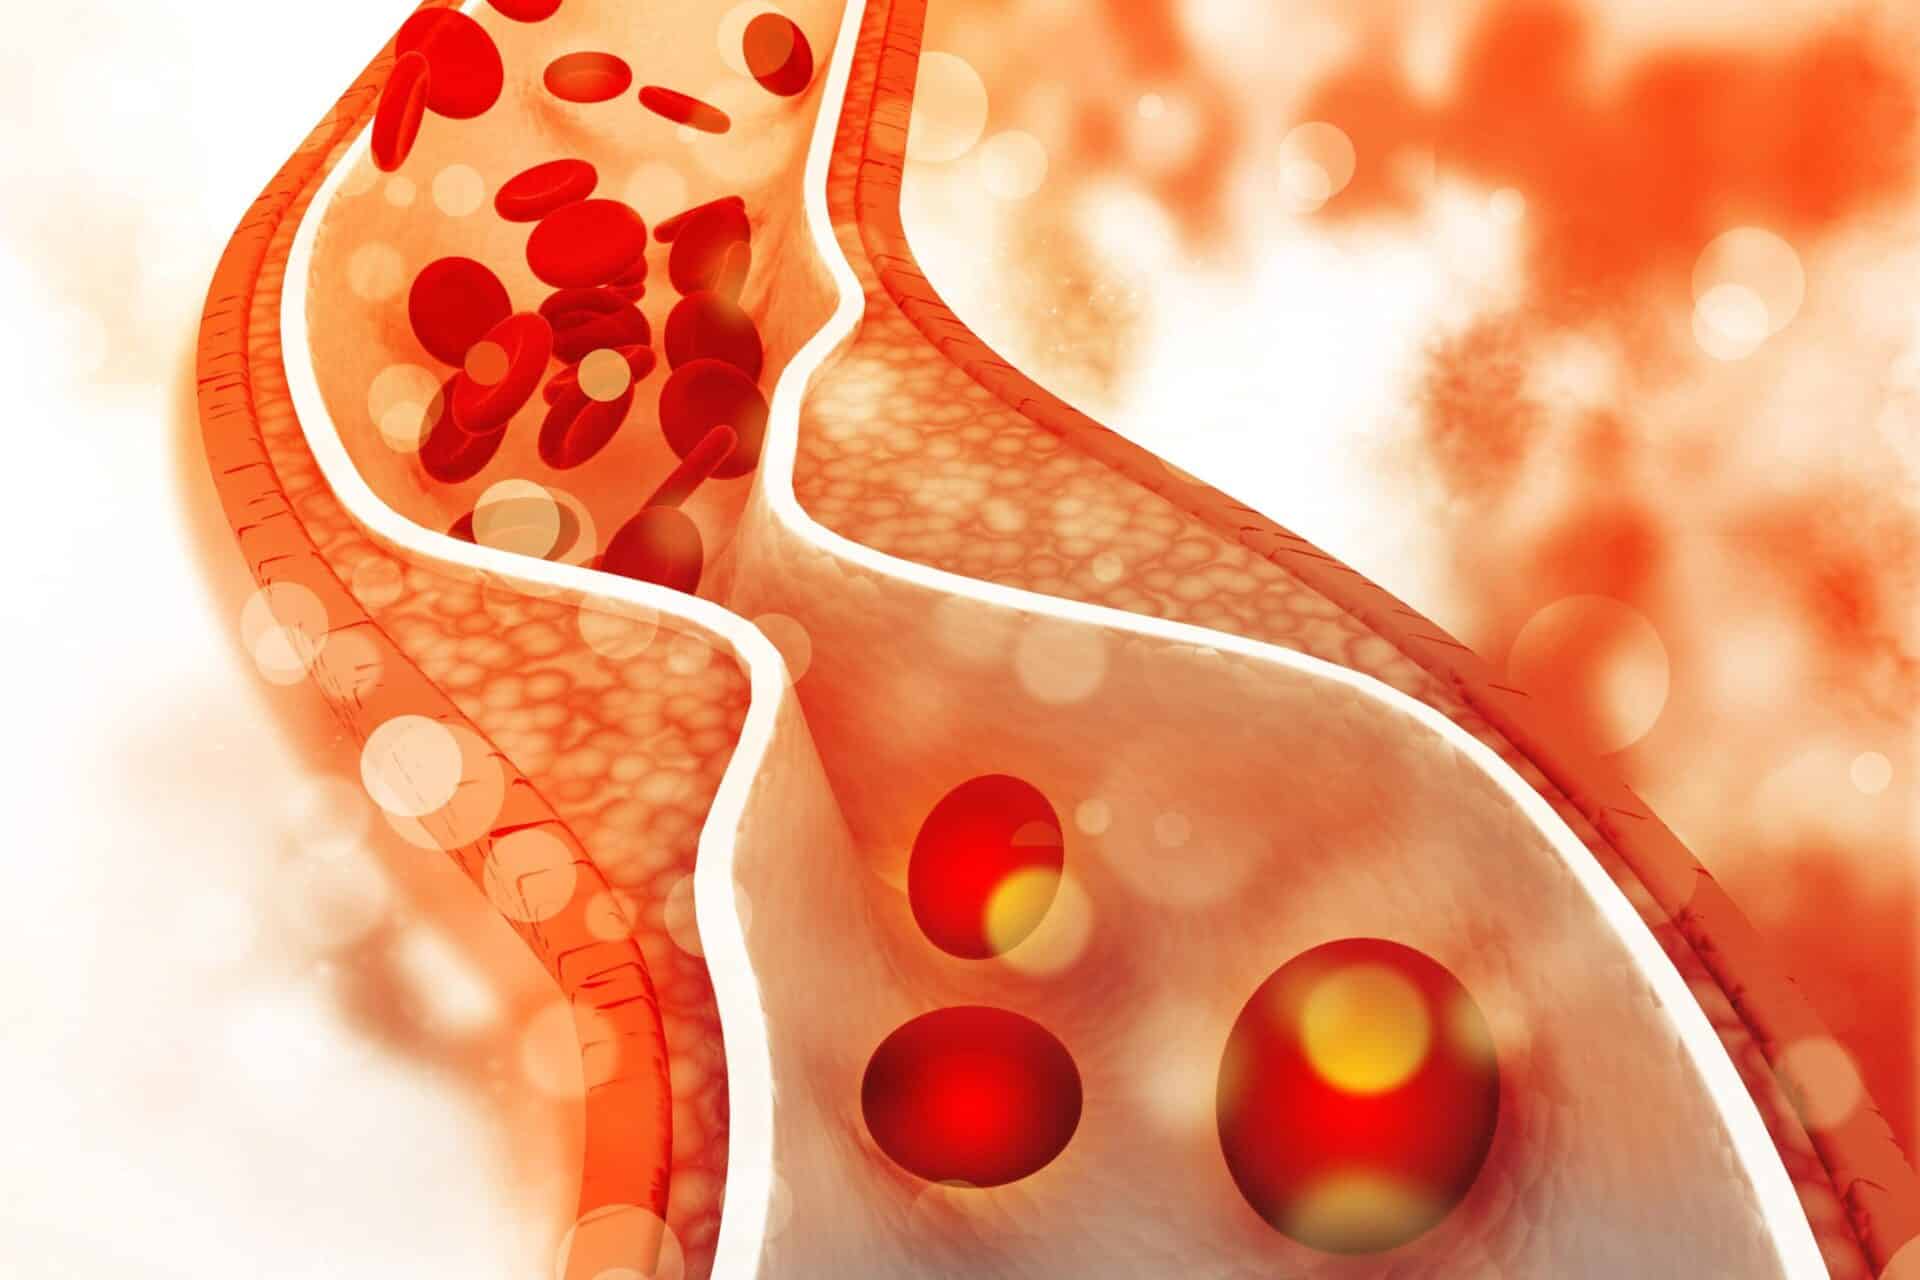

Υψηλή χοληστερίνη αποτελεί μια από τις πιο διαδεδομένες αιτίες καρδιαγγειακών νοσημάτων, αυξάνοντας τον κίνδυνο εμφάνισης έμφραγματος, εγκεφαλικού και άλλων σοβαρών παθήσεων. Οι παραδοσιακές θεραπείες, όπως η χρήση στατινών, έχουν βοηθήσει πολλούς ασθενείς στη διαχείριση των επιπέδων χοληστερίνης, ωστόσο συχνά συνοδεύονται από παρενέργειες και δεν είναι αποτελεσματικές σε όλους.

Η πρωτεΐνη PCSK9 λειτουργεί ως ρυθμιστής, που μειώνει την απομάκρυνση της LDL χοληστερίνης από το αίμα, με αποτέλεσμα την αύξηση των επιπέδων της. Με τη χρήση της τεχνολογίας CRISPR, οι επιστήμονες μπορούν να «απενεργοποιήσουν» το γονίδιο που κωδικοποιεί την PCSK9, μειώνοντας έτσι την παραγωγή της και επιτυγχάνοντας σημαντική μείωση της «κακής» χοληστερίνης.